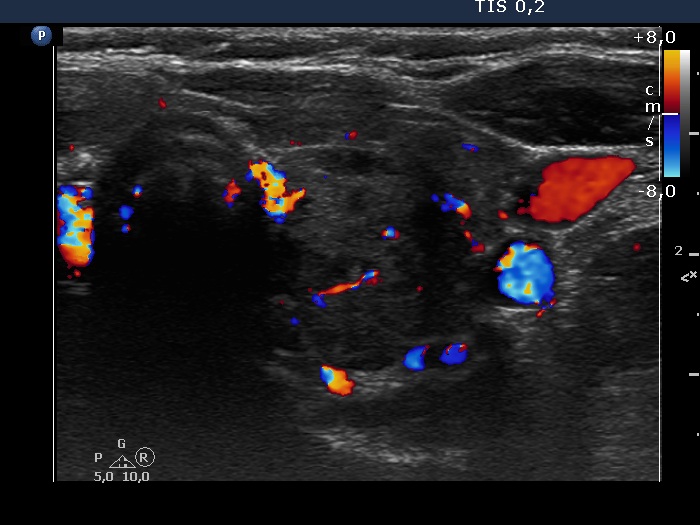

Consecutive patients with the final diagnosis of Hashimoto's thyroiditis - 63 (1001) (ultrasonographic picture 9)

Left lobe, transverse scan, color Doppler mode. The vascularization is a bit increased.